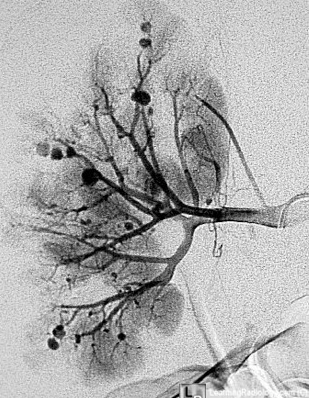

31-year-old woman presented to the Emergency Department with severe headache and visual changes. She also described fatigue, a 7-lb weight loss, and low-grade fever for the last month. BP is 219/112 mm Hg in both arms and legs. Blurred optic disc margins and retinal hemorrhages are observed on eye exam. No abdominal bruits were noted. Labs: hemoglobin, 10.7 g/dL; platelet count, 225 × 1000/μl, and peripheral smear without schistocytes. Serum electrolytes: Na, 135 mEq/L; K, 3.1 mEq/L; and HCO3, 26 mEq/L. Blood urea nitrogen level was 45 mg/dL, and serum creatinine was 1.7 mg/dL. Urinalysis: specific gravity, 1.012; pH 6.0, trace protein. Urine microscopy: 2-5 granular casts/LPF and 2-5 RTE cells/HPF.

A

Classical polyarteritis nodosa (PAN)

Arteriogram demonstrates multiple aneurysms and irregular constrictions in the larger vessels with occlusion of smaller penetrating arteries in the kidneys consistent with PAN